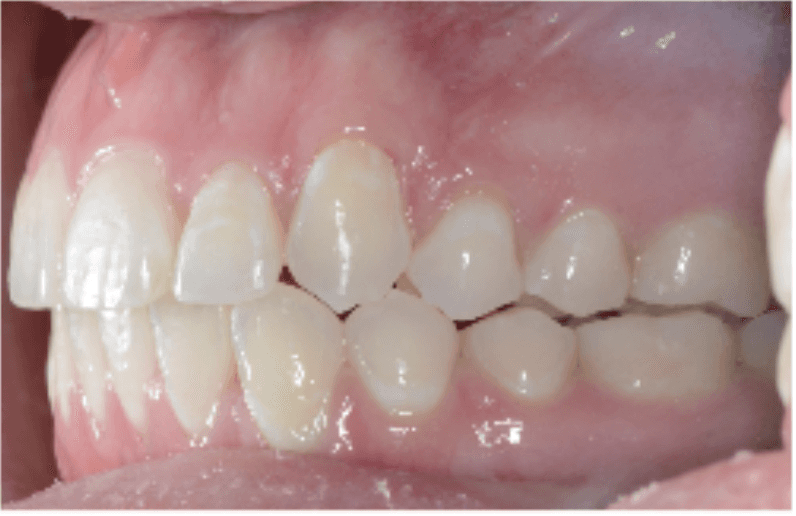

Initial treatment

INTRAORAL